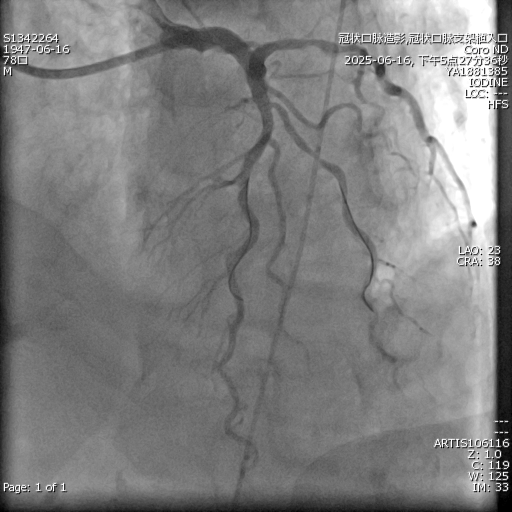

震波球囊「破壁」:采用震波球囊技术,通过精准释放冲击波有效碎裂深层钙化病灶,为支架植入开辟通路;

IVUS 精准导航:通过血管内超声实时引导,确保支架精准定位,完美贴合血管壁。

在团队紧密配合下,手术历时 2 小时顺利完成。术后患者血管恢复正常,症状明显改善,于 6 月 23 日康复出院。